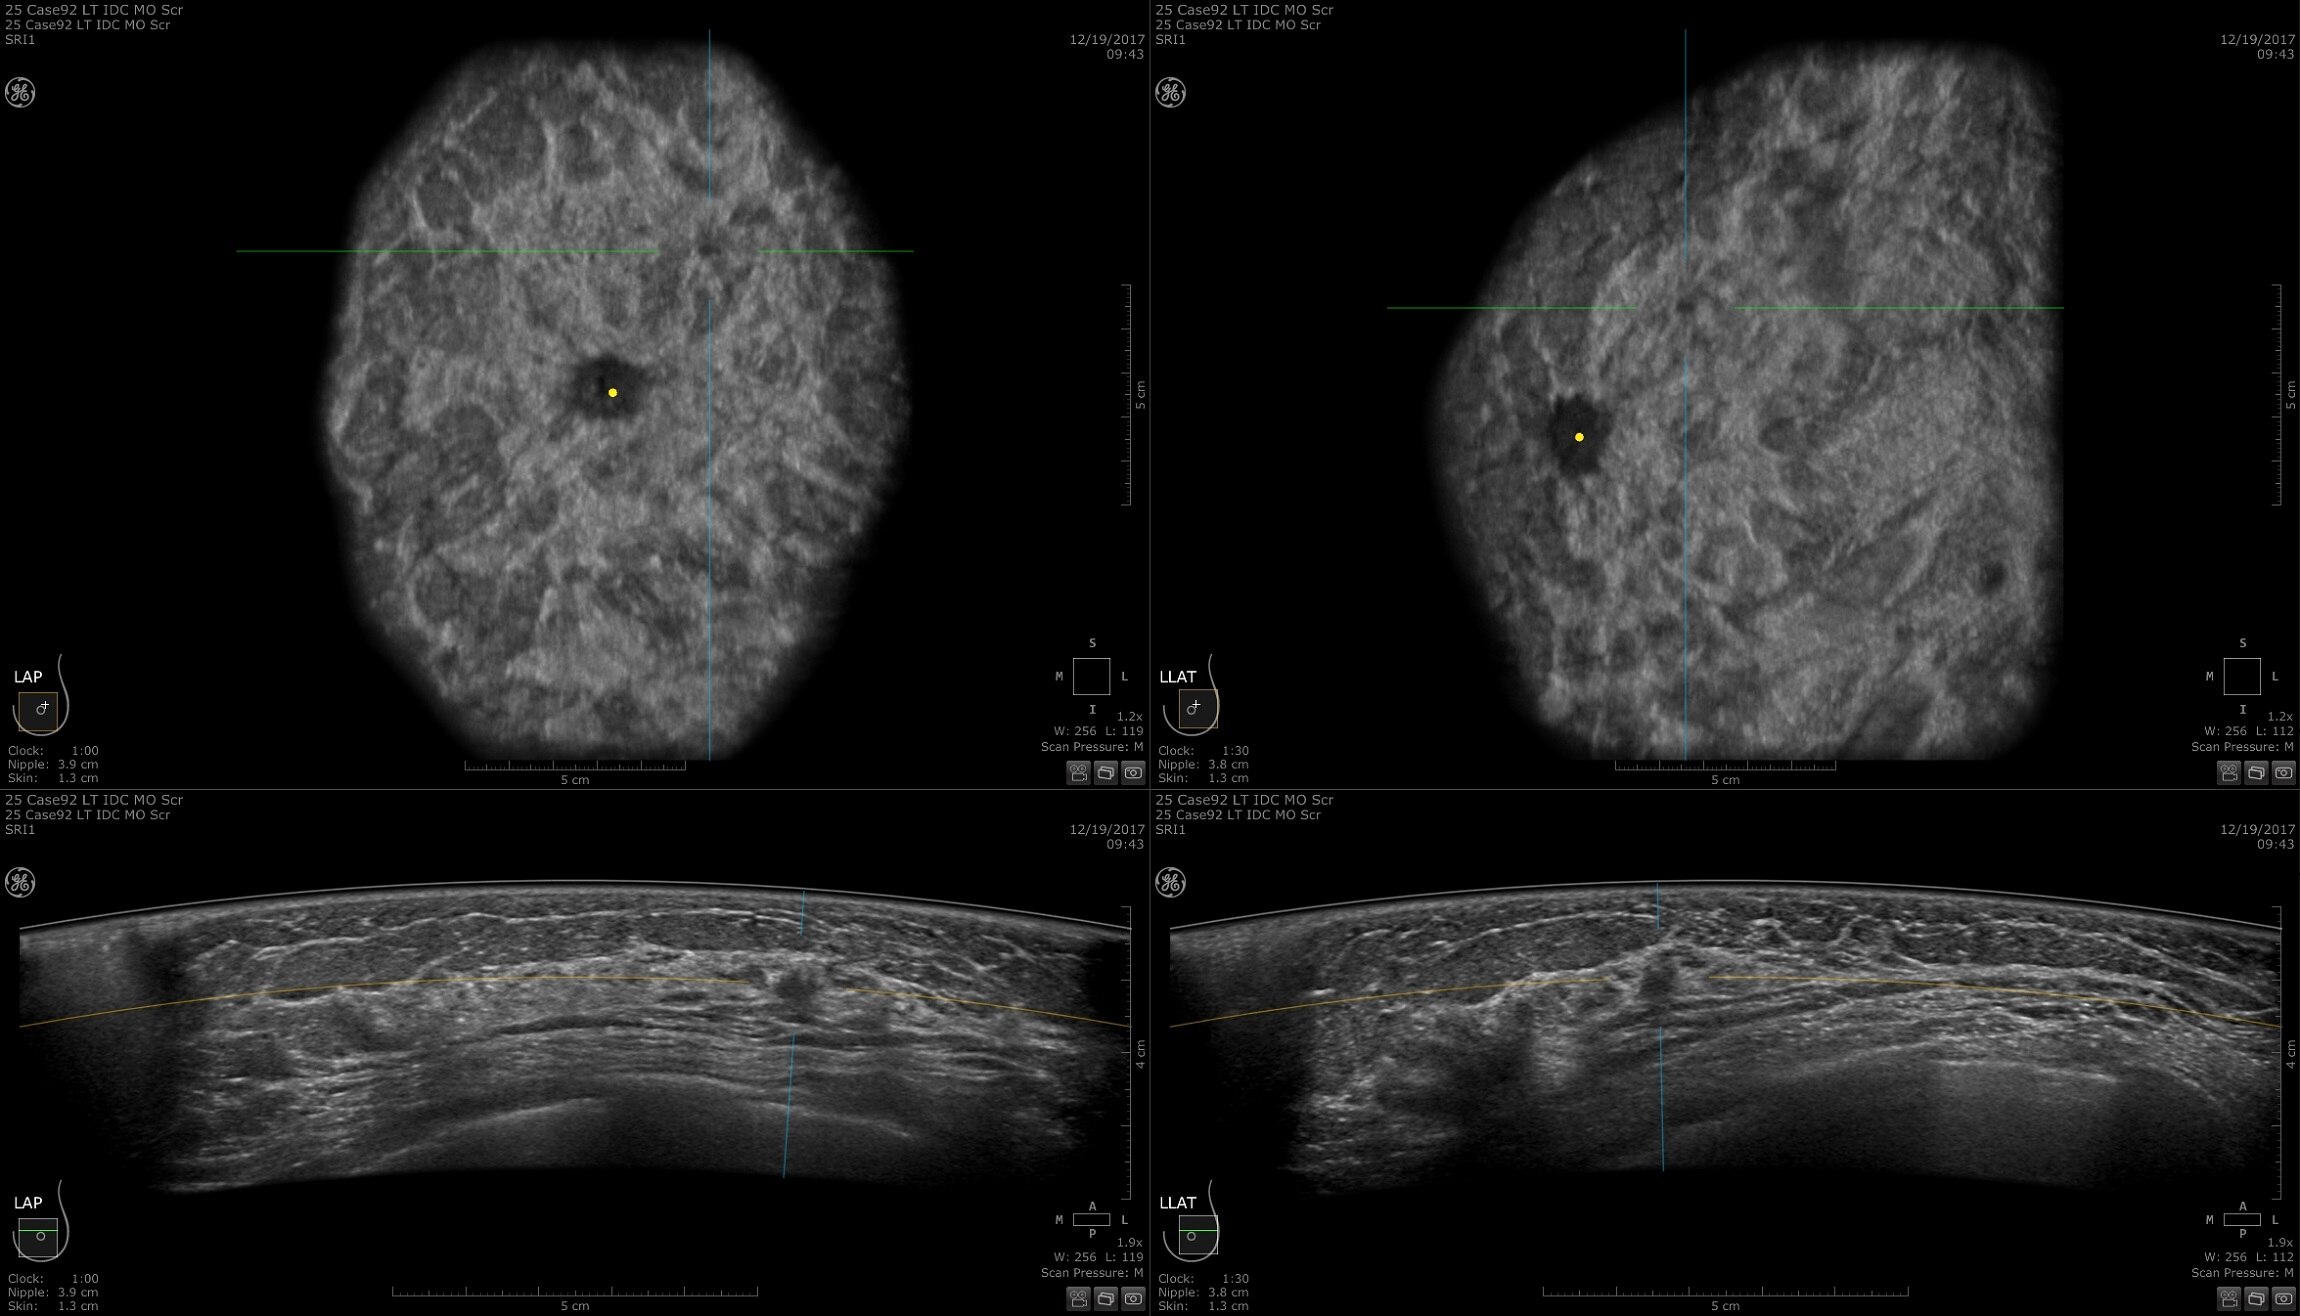

Maggiore nitidezza nell'imaging con il deep learning

Miglioramento delle prestazioni